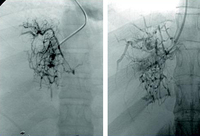

Budd-Chiari syndrome

Tests for prothrombotic conditions in patients with Budd-Chiari syndrome

From the personal collection of Soha Saoud Abdel Moneim, MD, PhD and Vijay H. Shah, MD; used with permission